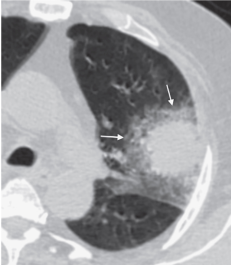

Симптом ободка

Определяется при КТ в виде перифокальной зоны уплотнения по типу матового стекла

Halo sign (син.: симптом ареола; не рекомендовано: симптом гало, симптом хало)

Определяется при КТ в виде перифокальной зоны уплотнения по типу матового стекла (см. Симптом матового стекла) вокруг участка консолидации (см.). Впервые был описан как признак геморрагии вокруг зоны консолидации при инвазивном аспергиллезе. Симптом не является специфичным и может проявляться при любых геморрагиях, ассоциированных с другими очаговыми поражениями легочной ткани, при локальном воспалении легочной ткани или опухолевых процессах (например, аденокарцинома).